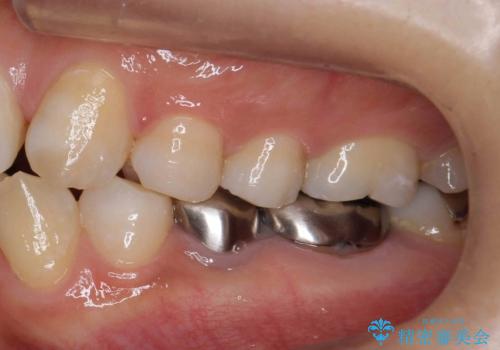

- 左下の銀歯二本のやりかえを希望。(左下5および左下6)

高さがないため、歯肉と歯槽骨の手術(歯周外科手術)APFを行ってから、最終的な被せ物にしました。

高さがない場合は、被せ物が外れやすくなります。高さを出すには向かいの歯を低くするか、まわりの歯茎を下げるか、になります。

今回は歯周外科処置を行い、歯の周りの歯肉の高さをさげるようにしました。